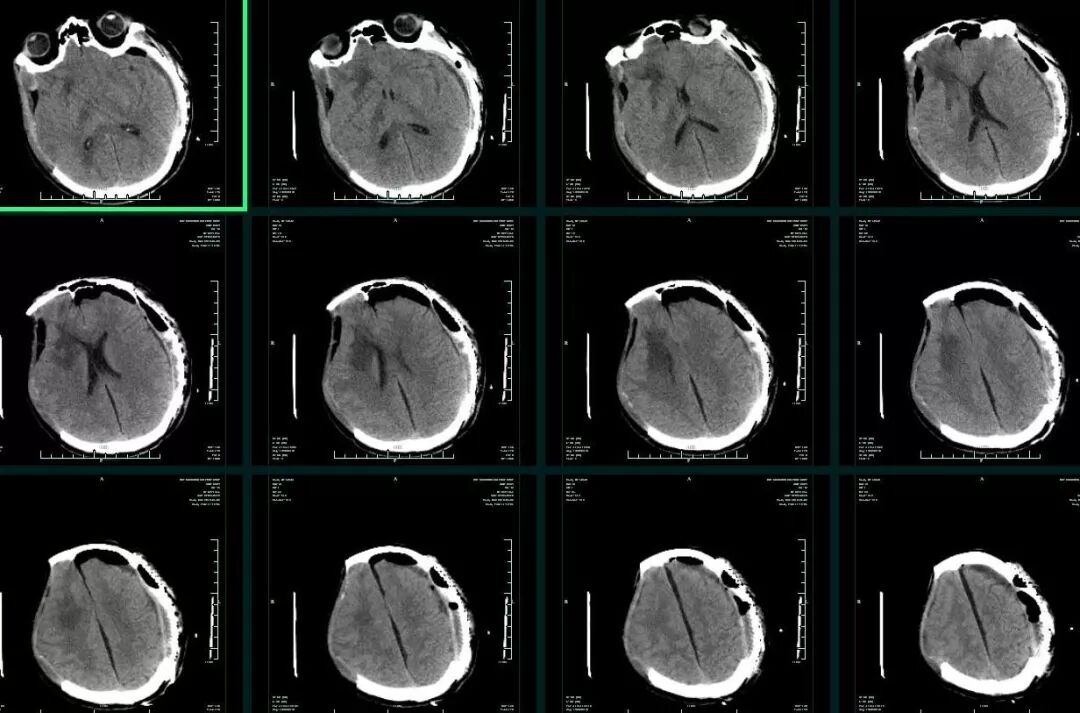

入院时患者深昏迷,GCS6分,左侧瞳孔0.5cm,右侧瞳孔0.3cm,对光反射均消失。急诊头颅CT提示:“左侧额颞顶部急性硬膜外血肿,脑疝(图1)”,急诊行左侧颅内血肿清除+去骨瓣减压术,术后即刻头颅CT复查提示:“右侧额颞叶急性硬膜下血肿”(图2),再次开颅行右侧颅内血肿清除+去骨瓣减压术。术后转ICU科呼吸支持治疗。术后再次复查CT,见血肿已清除,无硬膜下积液,中线基本居中(图3)。术后5天患者病情好转,GCS8分,双侧瞳孔0.3cm,对光反射迟钝,转回神经外科监护病房。

图1. 急诊头颅CT提示:左侧额颞顶部急性硬膜外血肿。